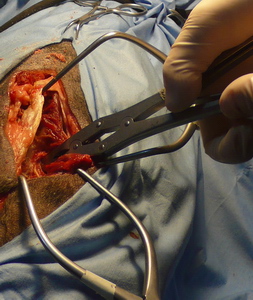

Fresando

Con el motor mellando la ventana

Agarnadando la ventana con el saca bocadosi